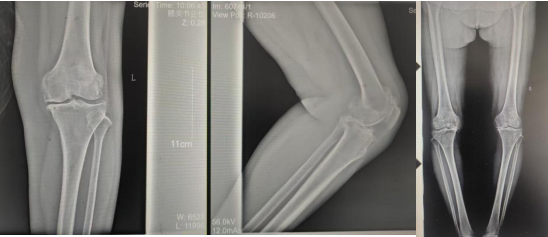

张女士于10年前劳累后左膝疼痛 ,,,,,干活后疼痛较重 ,,,,,阴雨天及受凉时疼痛显着 ,,,,,行走时可闻及枢纽内异响 ,,,,,时有“打软腿”征象 ,,,,,曾到周围多家医院诊治 ,,,,,给予膝枢纽针灸、膏药外贴、口服药物等“守旧”治疗 ,,,,,治疗后疼痛症状略有好转 ,,,,,但易复发;;近2年患者左膝枢纽疼痛逐渐加重 ,,,,,行走跛行 ,,,,,下蹲及上下楼梯难题 ,,,,,活动时疼痛显着 ,,,,,休息、守旧治疗后疼痛无显着好转。。。。。。

张女士的邻人看她上下楼云云难题 ,,,,,日常生涯都很受影响 ,,,,,因其以前在我院看过腰椎 ,,,,,效果优异 ,,,,,故先容张女士来我院找万昌胜主治医师举行咨询问诊。。。。。。万医生相识情形后带她到我院枢纽外科举行更专业的诊治。。。。。。枢纽外科门诊医师连系症状体征及影像学检查 ,,,,,建议入院手术治疗 ,,,,,以“左膝骨性枢纽炎伴膝内翻、高血压病”收住入院。。。。。。

术前影像资料

365英国上市(集团)有限公司-Official website